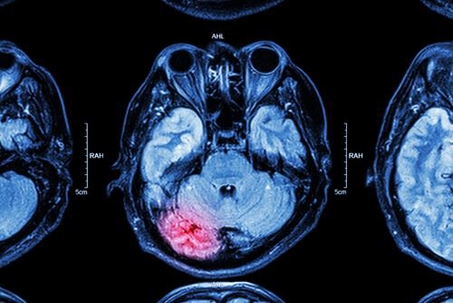

brain image